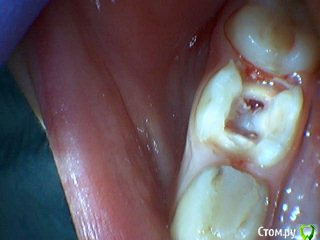

Давлетшин Опубликовано 29 декабря, 2017 Поделиться Опубликовано 29 декабря, 2017 (изменено) Друзья. Расскажите, не поменялось ли ваше отношение к пульпотеку и пр.Почему пломбы поверх пульпотеку такие ужасно жёлтые? Что сделать можно. Или что я делаю не так? "Друзья" так приятно перед новым годом. К пульпотеку не поменялось (устраивает вполне) , к пульподенту скептическое отношение, хоть и тоже работаю. Пломбы сразу желтые или через полгода - год- два? Очень тяжело что то советовать он лайн не видя как человек работает. В фото первая цифра пациент, вторая-третья номер зуба, четвертая порядок фото. Я после наложения пульпотека , стараюсь убрать излишки, или аккуратно на устья каналов накладываю, в пульповую камеру СИЦ, и сверху пломбу, Убрать излишки и со стенок, аккуратно в том числе и бором. В третьем клиническом случае, неудача. Зуб удалил сам же через 3 месяца. причину вижу в том что на рентгене не увидел (или так сделали снимок?) вертикальный тип рассасывания практически до бифуркации., может и потому что ребенок ОЧЕНЬ плохо сидел. За фото не пинайте сильно, не инстаграмм все таки,да и тяжело ребенка лечить и фотки делать. или наоборот пинайте может лучше начнем фоткать. P.s. Добавлю протокол как лечу с пульпотеком, хр.фибр.пульпит1. анестезия2. кофер ( если дает)3. раскрытие кариозной и пульповой камеры4. удаление коронковой пульпы маленьким эскаватором, я стараюсь "отрубать" пульпу5. остановка кровотечения сухим ватным шариком, 0,5-1-2 минуты6. пульпотек на устья7 СИЦ в пульповую камеру8 со стенок остатки пульпотека соскребаю бором фиссурным , цилиндрическим, там же фальц9. Пломба. может что то и зыбыл ну и оценка только позитивная перед НГ Изменено 29 декабря, 2017 пользователем Давлетшин 2 Ссылка на комментарий